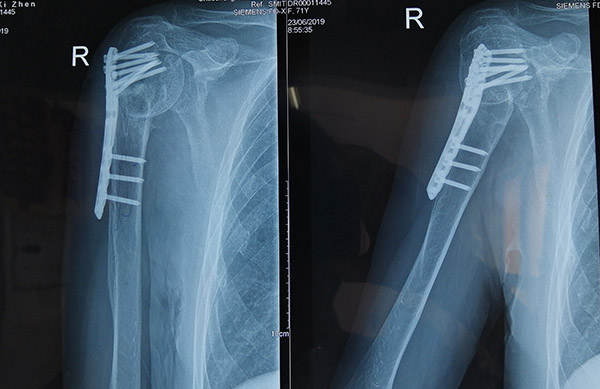

日前,吳阿姨來到愛心醫(yī)院骨科病區(qū)尋求幫助,要求醫(yī)生給她取出放置在肩膀內(nèi)的固定物。檢查后發(fā)現(xiàn),吳阿姨肩膀內(nèi)固定裝置的螺絲釘已穿出肱骨頭,骨折的部位因復(fù)位不良導(dǎo)致骨頭畸形愈合,這些成為吳阿姨長達一年多疼痛的根源。

6月28日,在朱剛主任帶領(lǐng)的骨科團隊通力協(xié)作下,歷經(jīng)兩個多小時,成功地為吳阿姨完成了內(nèi)固定裝置取出+右肩關(guān)節(jié)置換手術(shù)。